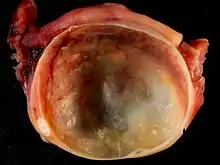

Histopathology

In case an ovarian cyst is surgically removed, a more definite diagnosis can be made by histopathology:

| Dermoid cyst | Well-differentiated components from at least two germ layers (ectoderm, mesoderm and/or endoderm).[22] | ![]() | |